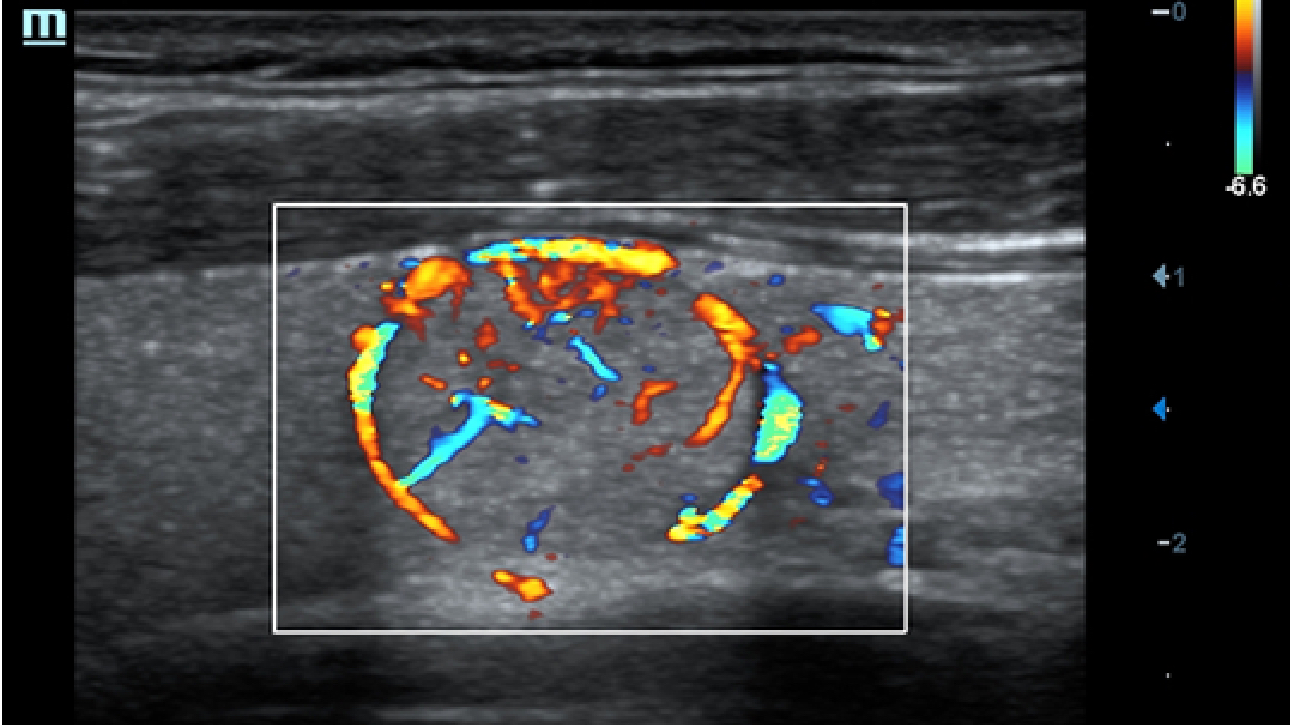

X-Insight is een inzichtelijke oplossing om meer visie te krijgen.

De gloednieuwe oplossing van Mindray is het geslaagde product dat is voortgekomen uit voortdurende klantinzichten in klinische behoeften in combinatie met steeds evoluerende, geavanceerde ultrasoundtechnologie?n. Vol energie en gebrand op toekomstgerichte inzichten en eindeloze mogelijkheden: dankzij de verhoogde schaalbaarheid wordt de oplossing continu verbeterd.

Als allround partner zet DC-60 Exp met X-Insight zich in om een allesomvattende oplossing te zoeken waarmee u alle aspecten van uw dagelijkse klinische activiteiten gemakkelijk en trefzeker kunt beheren.

De DC-60 Exp met X-Insight is ontworpen op basis van diepgaand inzicht in klantbehoeften om hoge effici?ntie met nauwkeurige beeldverwerking te leveren, dankzij eXacte helderheid, eXceptionele intelligentie en eXcellente ervaring.